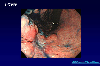

A case of multiple gastric cancer in which small cell carcinoma and adenocarcinoma synchronously developed.

Endoscopy